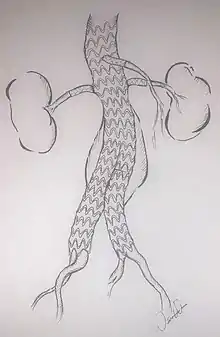

Fenestrated endovascular aortic/aneurysm repair (FEVAR) is performed in the cases where the aneurysm extends near or involves the visceral vessels (such as juxta-renal, para-renal, thoraco-abdominal aortic aneurysms). A custom-made graft with fenestrations (holes on the graft body to maintain the patency of the visceral arteries) is used for the procedure. When the aneurysm involves the visceral arteries, standard EVAR is contraindicated due to the lack of suitable infra-aortic segment for the endograft attachment; FEVAR achieves seal between the stent graft and para-visceral segment and/or more proximal segment while preserving the flow of the visceral arteries. FEVAR has been in use in the United Kingdom for over a decade and early results were published in Jun 2012. [16]

Thoracoabdominal aortic aneurysms (TAAA) involve the aorta in the chest and abdomen. As such, major branch arteries to the head, arms, spinal cord, intestines, and kidneys may originate from the aneurysm. An endovascular repair of a TAAA is only possible if blood flow to these critical arteries is preserved. Hybrid procedures offer one option, but a more direct approach involves the use of a branched endograft. However, the complex anatomy associated with the supra-aortic vessels is particularly difficult to accommodate with branched endograft devices.[17] Dr. Timothy Chuter pioneered this approach, with a completely endovascular solution. After partial deployment of the main body of an endograft, separate endograft limbs are deployed from the main body to each major aortic branch. This procedure is long, technically difficult, and currently only performed in a few centers. When the aneurysm begins above the renal arteries, neither fenestrated endografts nor "EndoAnchoring" of an infrarenal endograft is useful (an open surgical repair may be necessary). Alternatively, a "branched" endograft may be used. A branched endograft has graft limbs that branch off of the main portion of the device to directly provide blood flow to the kidneys or the visceral arteries.[18][19]